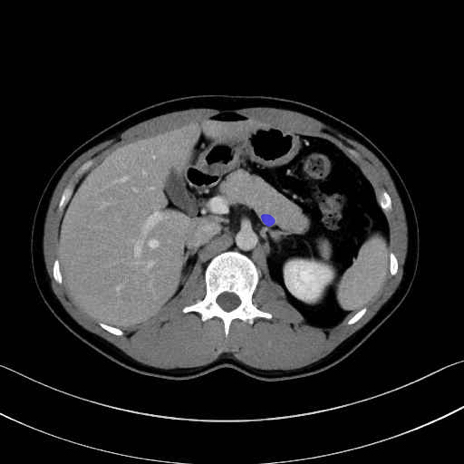

脾静脈の画像解剖

■起始:脾門で脾静脈枝が合流して本幹を形成。

■走行:膵体尾部の後面溝を右走し、膵頸部の後方で上腸間膜静脈(SMV)と合流して門脈を形成。

■主な流入枝:短胃静脈・左胃大網静脈・膵静脈、そして下腸間膜静脈(IMV)(変異あり)。